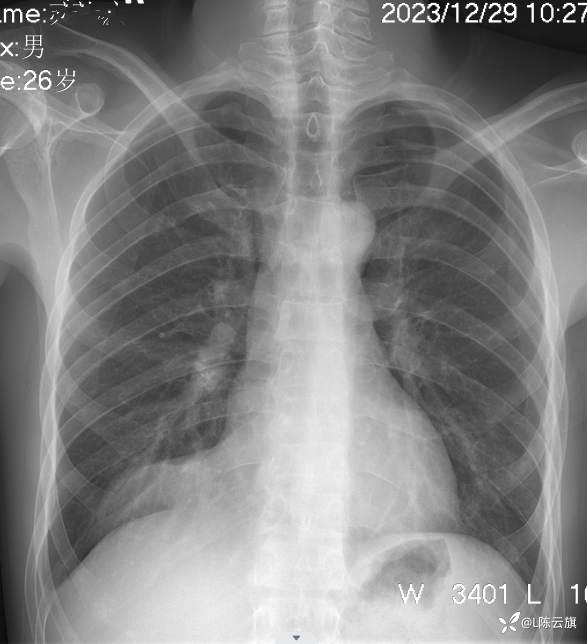

1、患者男,26岁,精神病住院患者。没有胸部及呼吸系统症状。正侧位胸片考虑什么?第一 次拟肺炎治疗后复查无改变!

2、平片所见:(CT随后上传!)